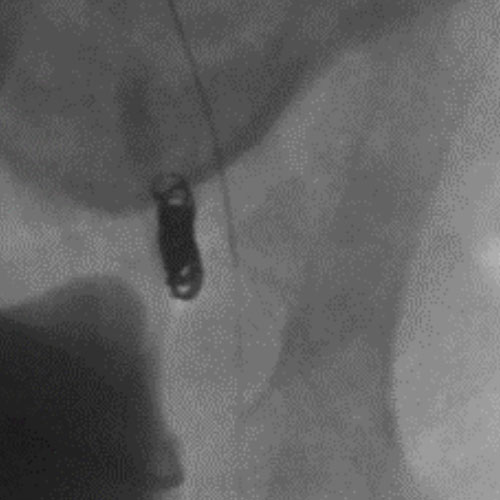

Ruby Standard Coil shown  in right subclavian medial Ruby Standard Coil shown in right subclavian medial

Right Subclavian Medial

3 Ruby Standard 6x20

Embold Fibered Coil shown  in left subclavian medial Embold Fibered Coil shown in left subclavian medial

Left Subclavian Medial

2 Embold Fibered Coil 6x20